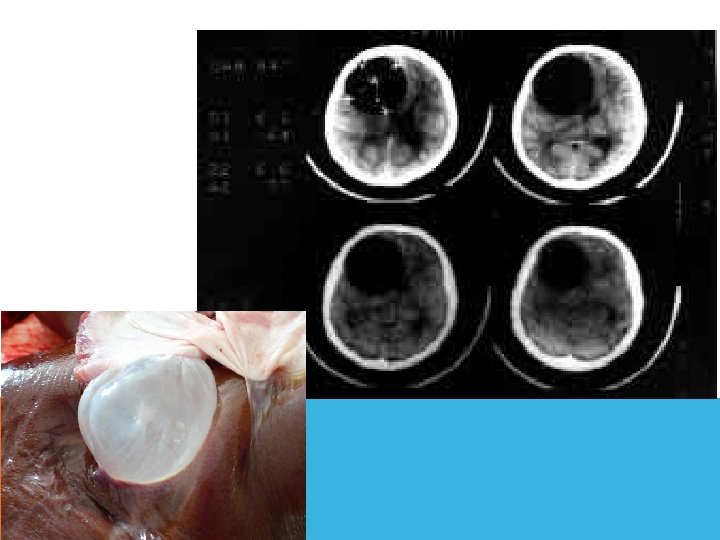

Абсцесс мозга Этиология. Пути проникновения инфекции: 1) путем контактного распространения (при гнойных заболеваниях среднего уха или околоносовых пазух – отиты, мастоидиты); 2) гематогенным путем; 3) через патологическое сообщение между полостью черепа и внешней средой (при проникающей ЧМТ, нейрохирургических манипуляциях, врожденных ликворных свищах).

Абсцесс Мозга

Патогенез Рост микроорганизмов. Локализованный энцефалит (церебрит) с отеком мозга. Гнойное расплавление очага Формирование капсулы. Клиническая картина Общеинфекционные симптомы (недомогание, лихорадка, тахикардия и т. д. ) Внутричерепная гипертензия Очаговые неврологические симптомы в зависимости от локализации абсцесса (эпилептические припадки, парезы, гемианопсия, афазии, мозжечковая симптоматика)

Диагностика Люмбальную пункцию не проводить! ОАК - лейкоцитоз и ускорение СОЭ. Рентгенография - наличие газа в полости черепа КТ абсцесс выглядит как зона низкой плотности с масс-эффектом. При введении конираста вокруг гиподенсивного центра выявляется тонкая кольцевидная гиперденсивная зона с ровными контурами. МРТ, абсцесс выглядит как относительно гомогенная гиперинтенсивная зона, имеющая слоистую структуру.

Наличие абсцесса является абсолютным показанием к оперативному лечению. Консервативная терапия показана при: обнаружении процесса на стадии энцефалита; небольшие размеры очага (обычно менее 2 см в диаметре); глубокое расположение абсцесса, что создает технические сложности и опасность значительной послеоперационной инвалидизации; наличие множественных абсцессов, которые невозможно дренировать; расположение абсцесса в критических зонах; наличие противопоказаний к оперативному вмешательству.